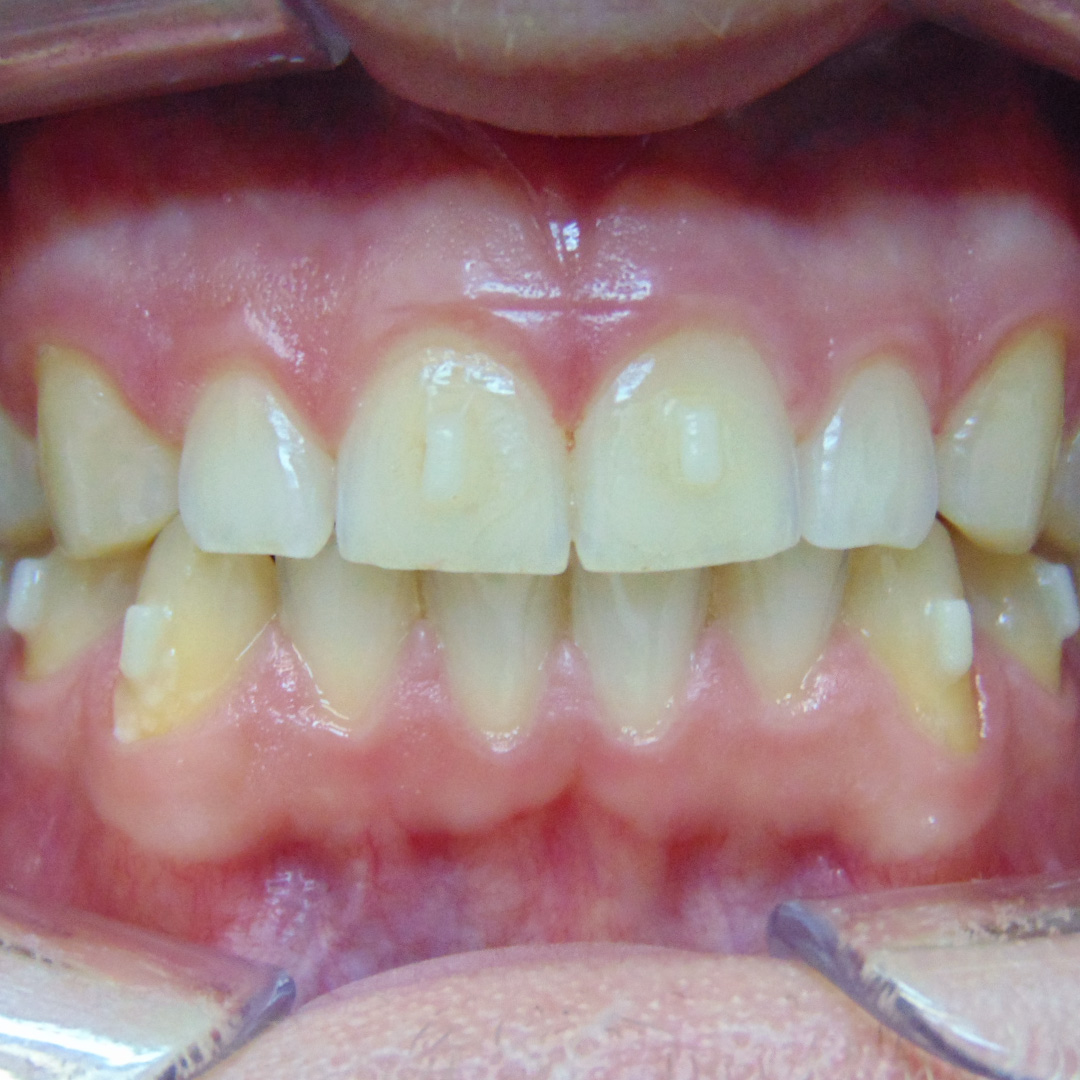

До и после лечения

В «Стоматологию Комфорта» обратился пациент с целью исправления нескольких дефектов прикуса. Проведя осмотр, врач-ортодонт Резниченко Анна Васильевна сделала заключение о наличии диастемы, тремы на верхней челюсти во фронтальном отделе. Также было диагностировано скученное положение зубов на нижней челюсти во фронтальном отделе. Врач принял решение об ортодонтическом лечении элайнерами 3D-smile.